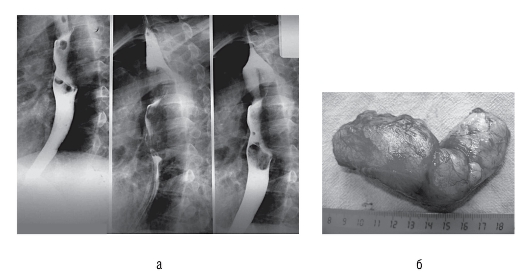

Рис. 30 (см. также цв. вклейку).Рентгенограмма пищевода (а) и удаленное новообразование (б) у больного, 52 лет

наличие подслизистой опухоли пищевода (рис. 30, б). Биопсия противопоказана из-за возможного повреждения слизистой оболочки, что в дальнейшем осложнит оперативное лечение и увеличит продолжительность госпитального периода.